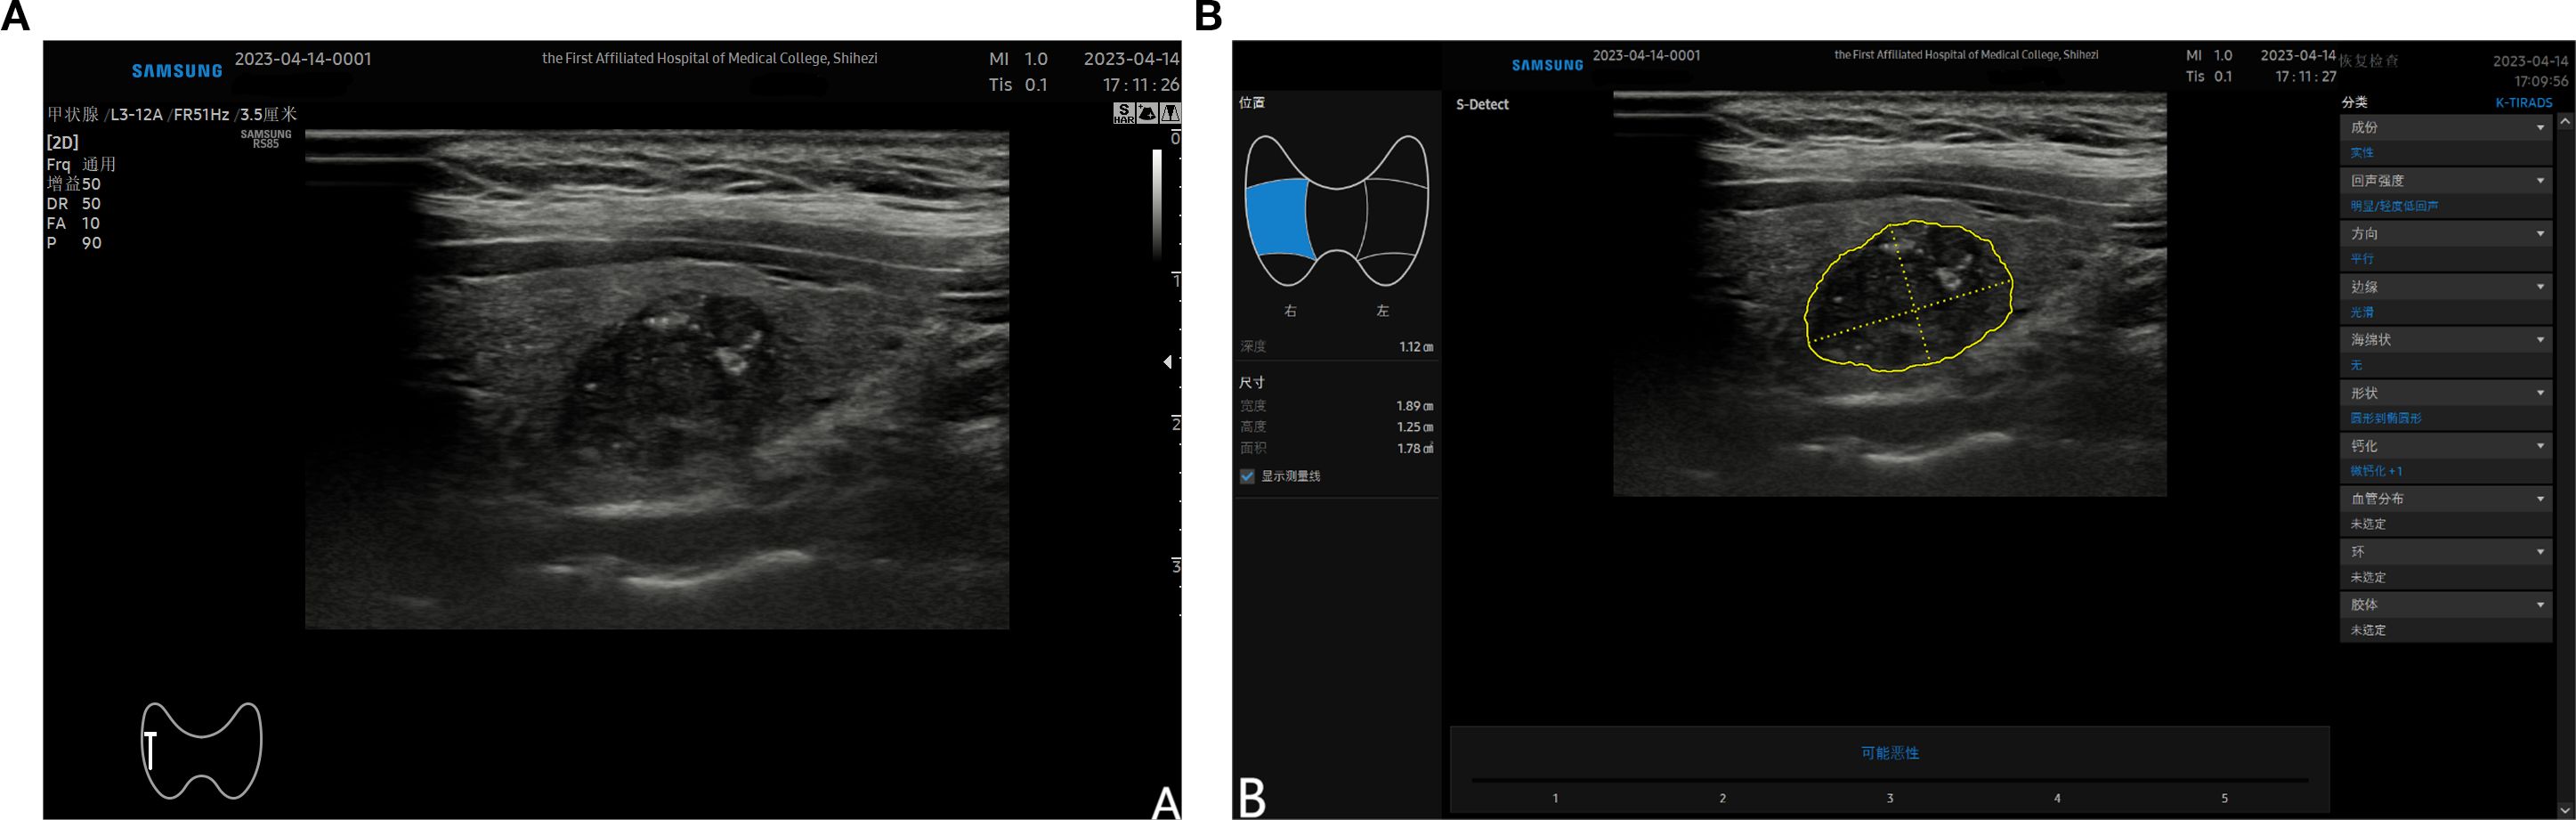

After completing the routine ultrasound examination, switchback to the standard two-dimensional ultrasound mode. Adjust the probe position to ensure the target nodule is clearly visible, aiming to achieve the maximum diameter of the nodule and a cross-section perpendicular to it, while clearly displaying the relationship between the nodule and surrounding tissues. Press the freeze button, fine-tune the trackball until the image is clear, enter S-Detect mode, and ensure the sampling box fully encompasses the target nodule. The program will automatically outline the nodule region; manually adjust or fine-tune by clicking if necessary. Finally, the program automatically analyzes the target region and provides an analysis result of “possibly malignant” or “possibly benign”, along with a structured report for reference. (Figure 2). This S-Detect examination was performed by a physician with over eight years’ experience in ultrasound, who is proficient in S-Detect operation techniques and was not involved in the conventional ultrasound imaging of the nodule previously. Throughout both the conventional ultrasound and S-Detect examinations, all clinicians remained blinded to the nodules’ final pathological findings. Furthermore, the clinician responsible for conventional ultrasound imaging and the clinician responsible for the S-Detect examination were mutually unaware of each other’s results.

Figure 2. (A) shows a malignant nodule located in the mid-section of the right lobe of the thyroid detected by ultrasound; (B) demonstrates the automatically outlined nodule area after entering the S-Detect mode and selecting the “auto tracing” option. The nodule characteristics are displayed on the right side of the screen, and the analysis results are shown at the bottom.